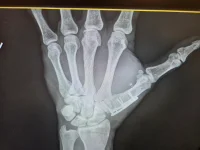

I also had hand surgery, 3 weeks after my back surgery. That was to resolve an old injury and deal with more arthritis. Picture attached; easier than an explanation. This is already too long. This has been and continues to be a difficult recovery. I still have a fair amount of pain and weakness in my hand and wrist. It's coming back, but slowly.

Attached are pix of my hand surgery and also a couple day old Pic of where I stand now at 190 lbs.